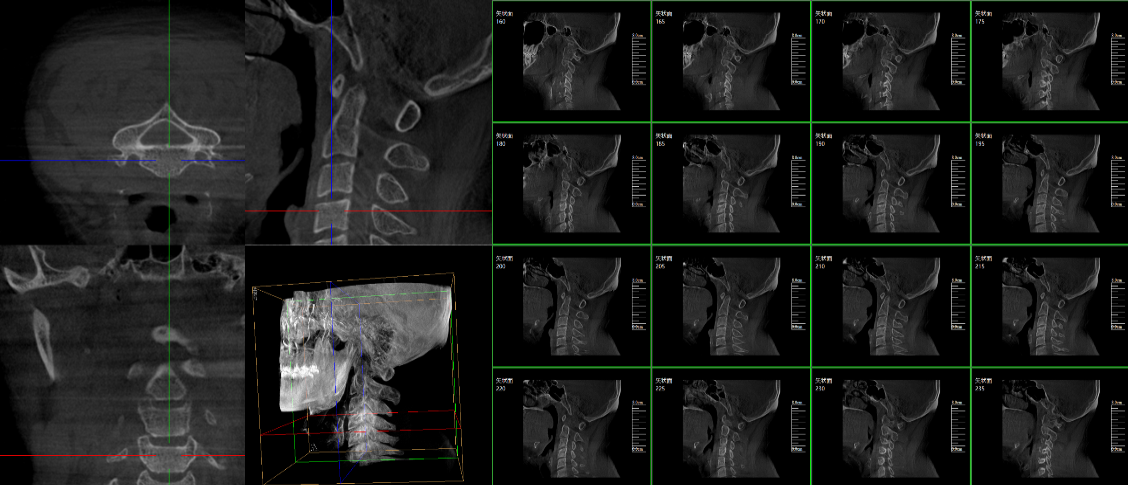

三維C臂,作為“術(shù)中CT”,能在術(shù)中快速地生成橫斷面、矢狀面、冠狀面和可旋轉(zhuǎn)的立體圖像,給術(shù)者提供360°無(wú)死角的觀察角度,全方位準(zhǔn)確判斷骨組織和植入物的情況,為手術(shù)的實(shí)施提供保障,極大提高手術(shù)成功率,減少并發(fā)癥概率。主要適用于骨科、脊柱外科、矯形外科、創(chuàng)傷骨科及手術(shù)室等。

普愛(ài)醫(yī)療三維C形臂具備術(shù)中實(shí)時(shí)三維成像,術(shù)中三維成像和橫斷面圖像提供多角度的手術(shù)診斷信息,輔助醫(yī)生進(jìn)行術(shù)中評(píng)估判斷,諸如骨折復(fù)位情況和內(nèi)植入螺釘?shù)某叽绾臀恢茫o助手術(shù)更好地完成;三維成像視野大,提供更大的術(shù)中三維成像視野,采集更多圖像信息,可一次拍全全段頸椎、全段腰椎、七節(jié)胸椎、雙側(cè)骶骼關(guān)節(jié)、股骨頭及單側(cè)盆骨等。如果您想了解更多普愛(ài)三維C形臂優(yōu)點(diǎn)及技術(shù)參數(shù),歡迎咨詢(xún)我們。